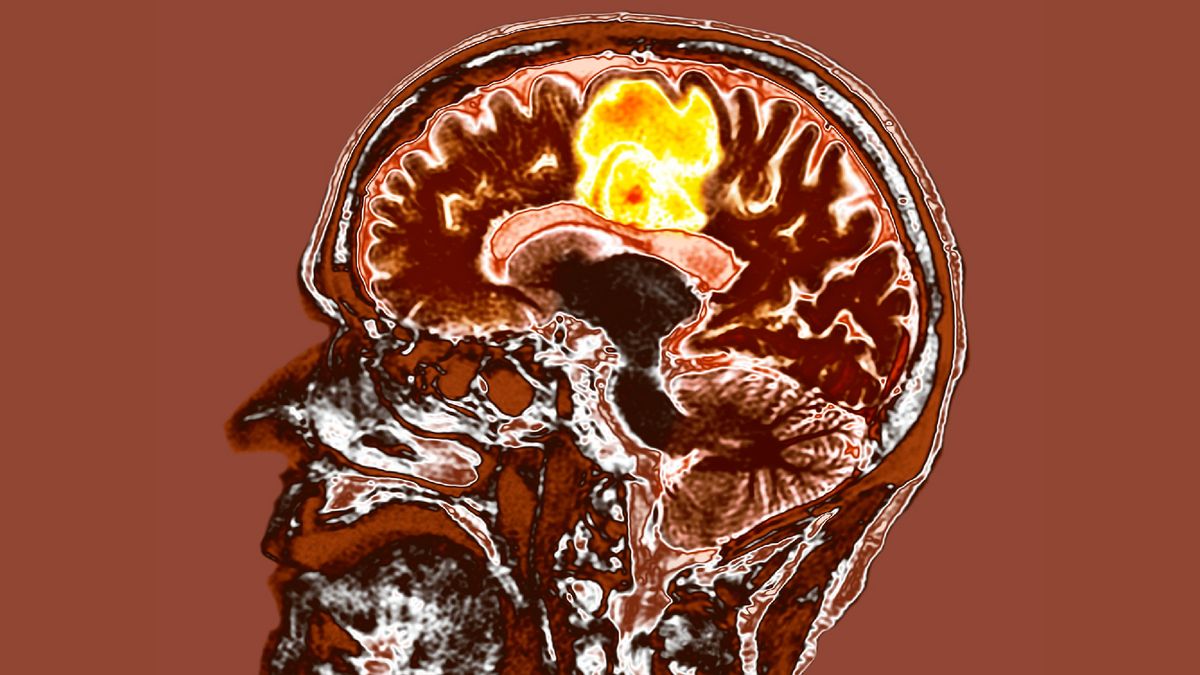

New treatment for most aggressive brain cancer may help patients live longer

Glioblastoma often kills within months. A new targeted radiation therapy may help patients live longer.